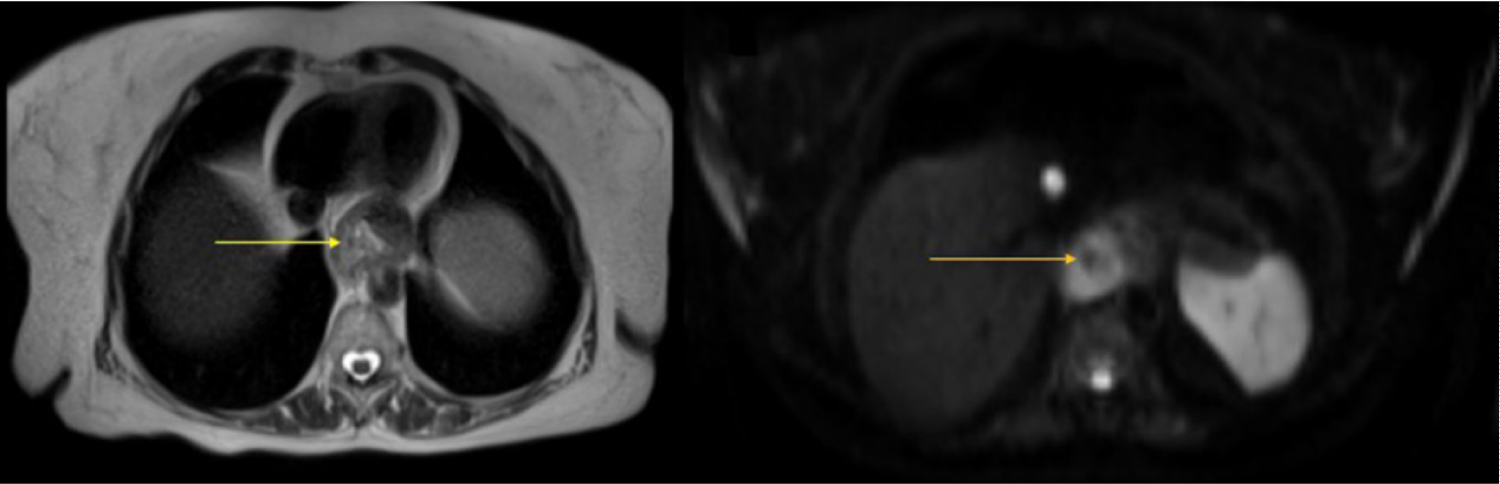

In June 2016, a new weekly chemotherapy regimen with Paclitaxel was begun. After 3 cycles, a PET-CT performed in January 2017 to evaluate response to treatment, found increased lymph nodes and liver subcapsular nodules in segment VI, suggesting progressing disease (PD) compared to the PET-CT in September 2016. Treatment with isolated Ramucirumab was started. In March 2017, Magnetic Resonance Imaging (MRI) showed progressive worsening nodal and liver PD (Figure 3 and Figure 4). Without the expected response to Ramucirumab, in May 2017, we changed the treatment line to Irinotecan alone. A PET-CT performed in June 2017 showed a favorable tumor response; however, partial treatment was instituted (dimensions of increased peritoneal thickening in iliac fossa were related to the increase in necrotic component and not to disease progression). Once isolated, the patient continued Irinotecan for 10 biweekly applications. In September 2017, an MRI revealed a liver nodule in the caudal aspect of segment IV with hypermetabolism signals, infectious and inflammatory changes involving the gallbladder and the liver parenchyma, and increased volume of the right ovary, which had a heterogeneous appearance. After 10 days, ultrasonography showed signs of cholecystitis and compression of the cystic duct by the hepatic hilum lymph node. During this period, the patient underwent microsatellite instability testing noting high instability (favorably to treatment with immunotherapy - being suggested for Pembrolizumab use). However, because immunotherapy treatment can only be initiated in the absence of inflammatory processes, a cholecystectomy was required. While awaiting surgery, the patient developed jaundice. Therefore, prosthesis installation was required in the common bile duct by Endoscopic Retrograde Cholangiopancreatography (ERCP), and during the procedure, we opted for permanent metal prosthesis. In September 2017, the patient underwent a cholecystectomy.

Figure 3: MRI showing an irregular parietal area with discharge at T2 (white arrow) and restriction to diffusion (yellow arrow) at DWI in the herniated gastric esophagus transition. View Figure 3